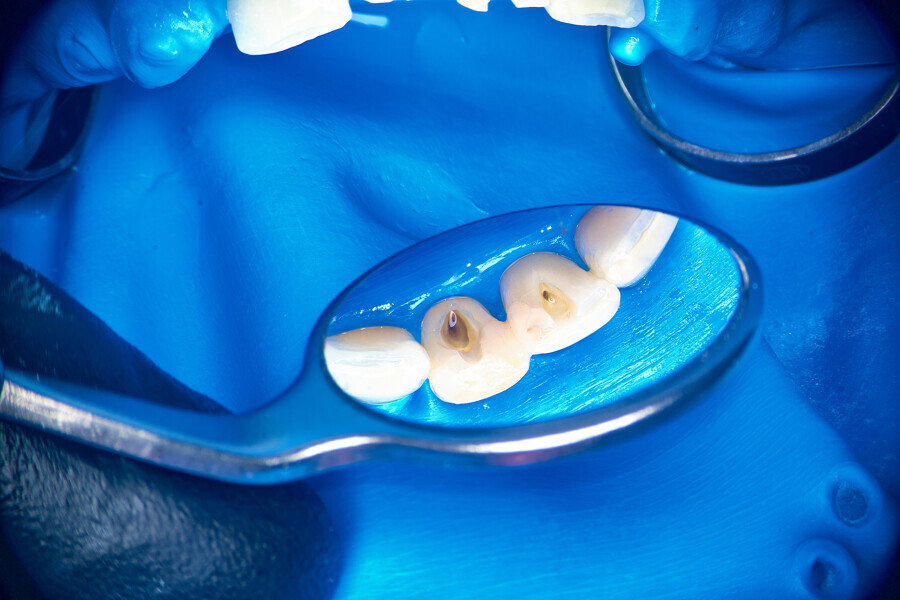

After local anaesthesia, the crown was cut with a high-speed handpiece (Fig. 25). The post was exposed and removed (Fig. 26 & 27). The pulp chamber and root canal orifices were examined for cracks. After inspection, a gingivectomy was performed (Fig. 28) and a dental dam (Kerr Dental) was placed (Fig. 29). The dental dam was sealed with a temporary flowable material (Fig. 30). After sealing the dental dam, the full adhesion protocol with a sixth-generation self-adhesive primer and bonding agent was performed, and the pre-endodontic build-up was created (Fig. 31). Residues of the cement and root canal filling materials were removed with a diamond-coated ultrasonic tip (Woodpecker; Fig. 32). Patency was easily established with hand files (VDW), and the canals were shaped with rotary martensitic files (Poldent) up to 40/0.04. Each step of instrumentation was performed with lubricating cream containing EDTA (VDW; Fig. 33). After each instrument, the canals were flushed with 5.25% sodium hypochlorite (Cerkamed). After reaching the final sizes of the root canals, the irrigation protocol was performed: three sequences of 5.25% sodium hypochlorite and 40.00% citric acid (Cerkamed) activated with an ultrasonic file (MANI), followed by 5.25% sodium hypochlorite activated with the ultrasonic file for approximately 10 minutes (Figs. 34 & 35). The flow of the liquid between both mesial canals was visible.

From this point of view, a novel approach of placing a tricalcium silicate-based sealer was a promising idea. The sealer was placed in the previously described manner. The premixed sealer in the plastic syringe (Meta Biomed) was placed in the mesiobuccal canal and the syringe depressed until it filled the mesiolingual canal. The distal canal was filled separately. In each canal, pistons from the previously heated gutta-percha extruder were placed and the warm gutta-percha was slightly compacted with stainless-steel hand condensers. A periapical radiograph was taken to evaluate the quality of the obturation. The bioceramic sealer was slightly extruded through the resorbed apex into the periapical area (Fig. 36). After the obturation, the chamber and orifices were cleaned (Fig. 37). A resin core with fibre posts was placed, and the temporary pink material was removed. The patient was referred to the prosthodontist for final restoration.